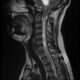

En primer lugar, la cirugía basada en la excelencia es científica en su naturaleza. Los cirujanos siguen rigurosamente los principios de la medicina basada en la evidencia, utilizando los últimos avances científicos y tecnológicos para tomar decisiones fundamentadas. Esto implica una comprensión profunda de la anatomía humana, la fisiología, la patología y los avances en la investigación médica. Los procedimientos quirúrgicos se basan en investigaciones previas y en la evidencia de su eficacia, lo que garantiza que se utilicen las técnicas más apropiadas y actualizadas.

Además, la cirugía basada en la excelencia se distingue por su enfoque en la seguridad del paciente. Antes de cualquier intervención quirúrgica, se realizan evaluaciones exhaustivas para determinar la aptitud del paciente y minimizar los riesgos asociados con la cirugía. Se siguen protocolos estrictos para prevenir infecciones, controlar la anestesia y garantizar un entorno quirúrgico estéril. Además, se realizan esfuerzos continuos para mejorar la seguridad quirúrgica, como la implementación de técnicas de cirugía mínimamente invasiva, que reducen el trauma y los tiempos de recuperación.

La efectividad es otro atributo clave de la cirugía basada en la excelencia. El objetivo principal es lograr los mejores resultados posibles para los pacientes. Esto implica una planificación cuidadosa y una ejecución precisa de los procedimientos quirúrgicos. Los cirujanos altamente capacitados y experimentados aplican su conocimiento y habilidades para abordar las necesidades individuales de cada paciente. Se hace un seguimiento cercano del progreso del paciente después de la cirugía para garantizar que se logren los resultados deseados y se realicen ajustes si es necesario.